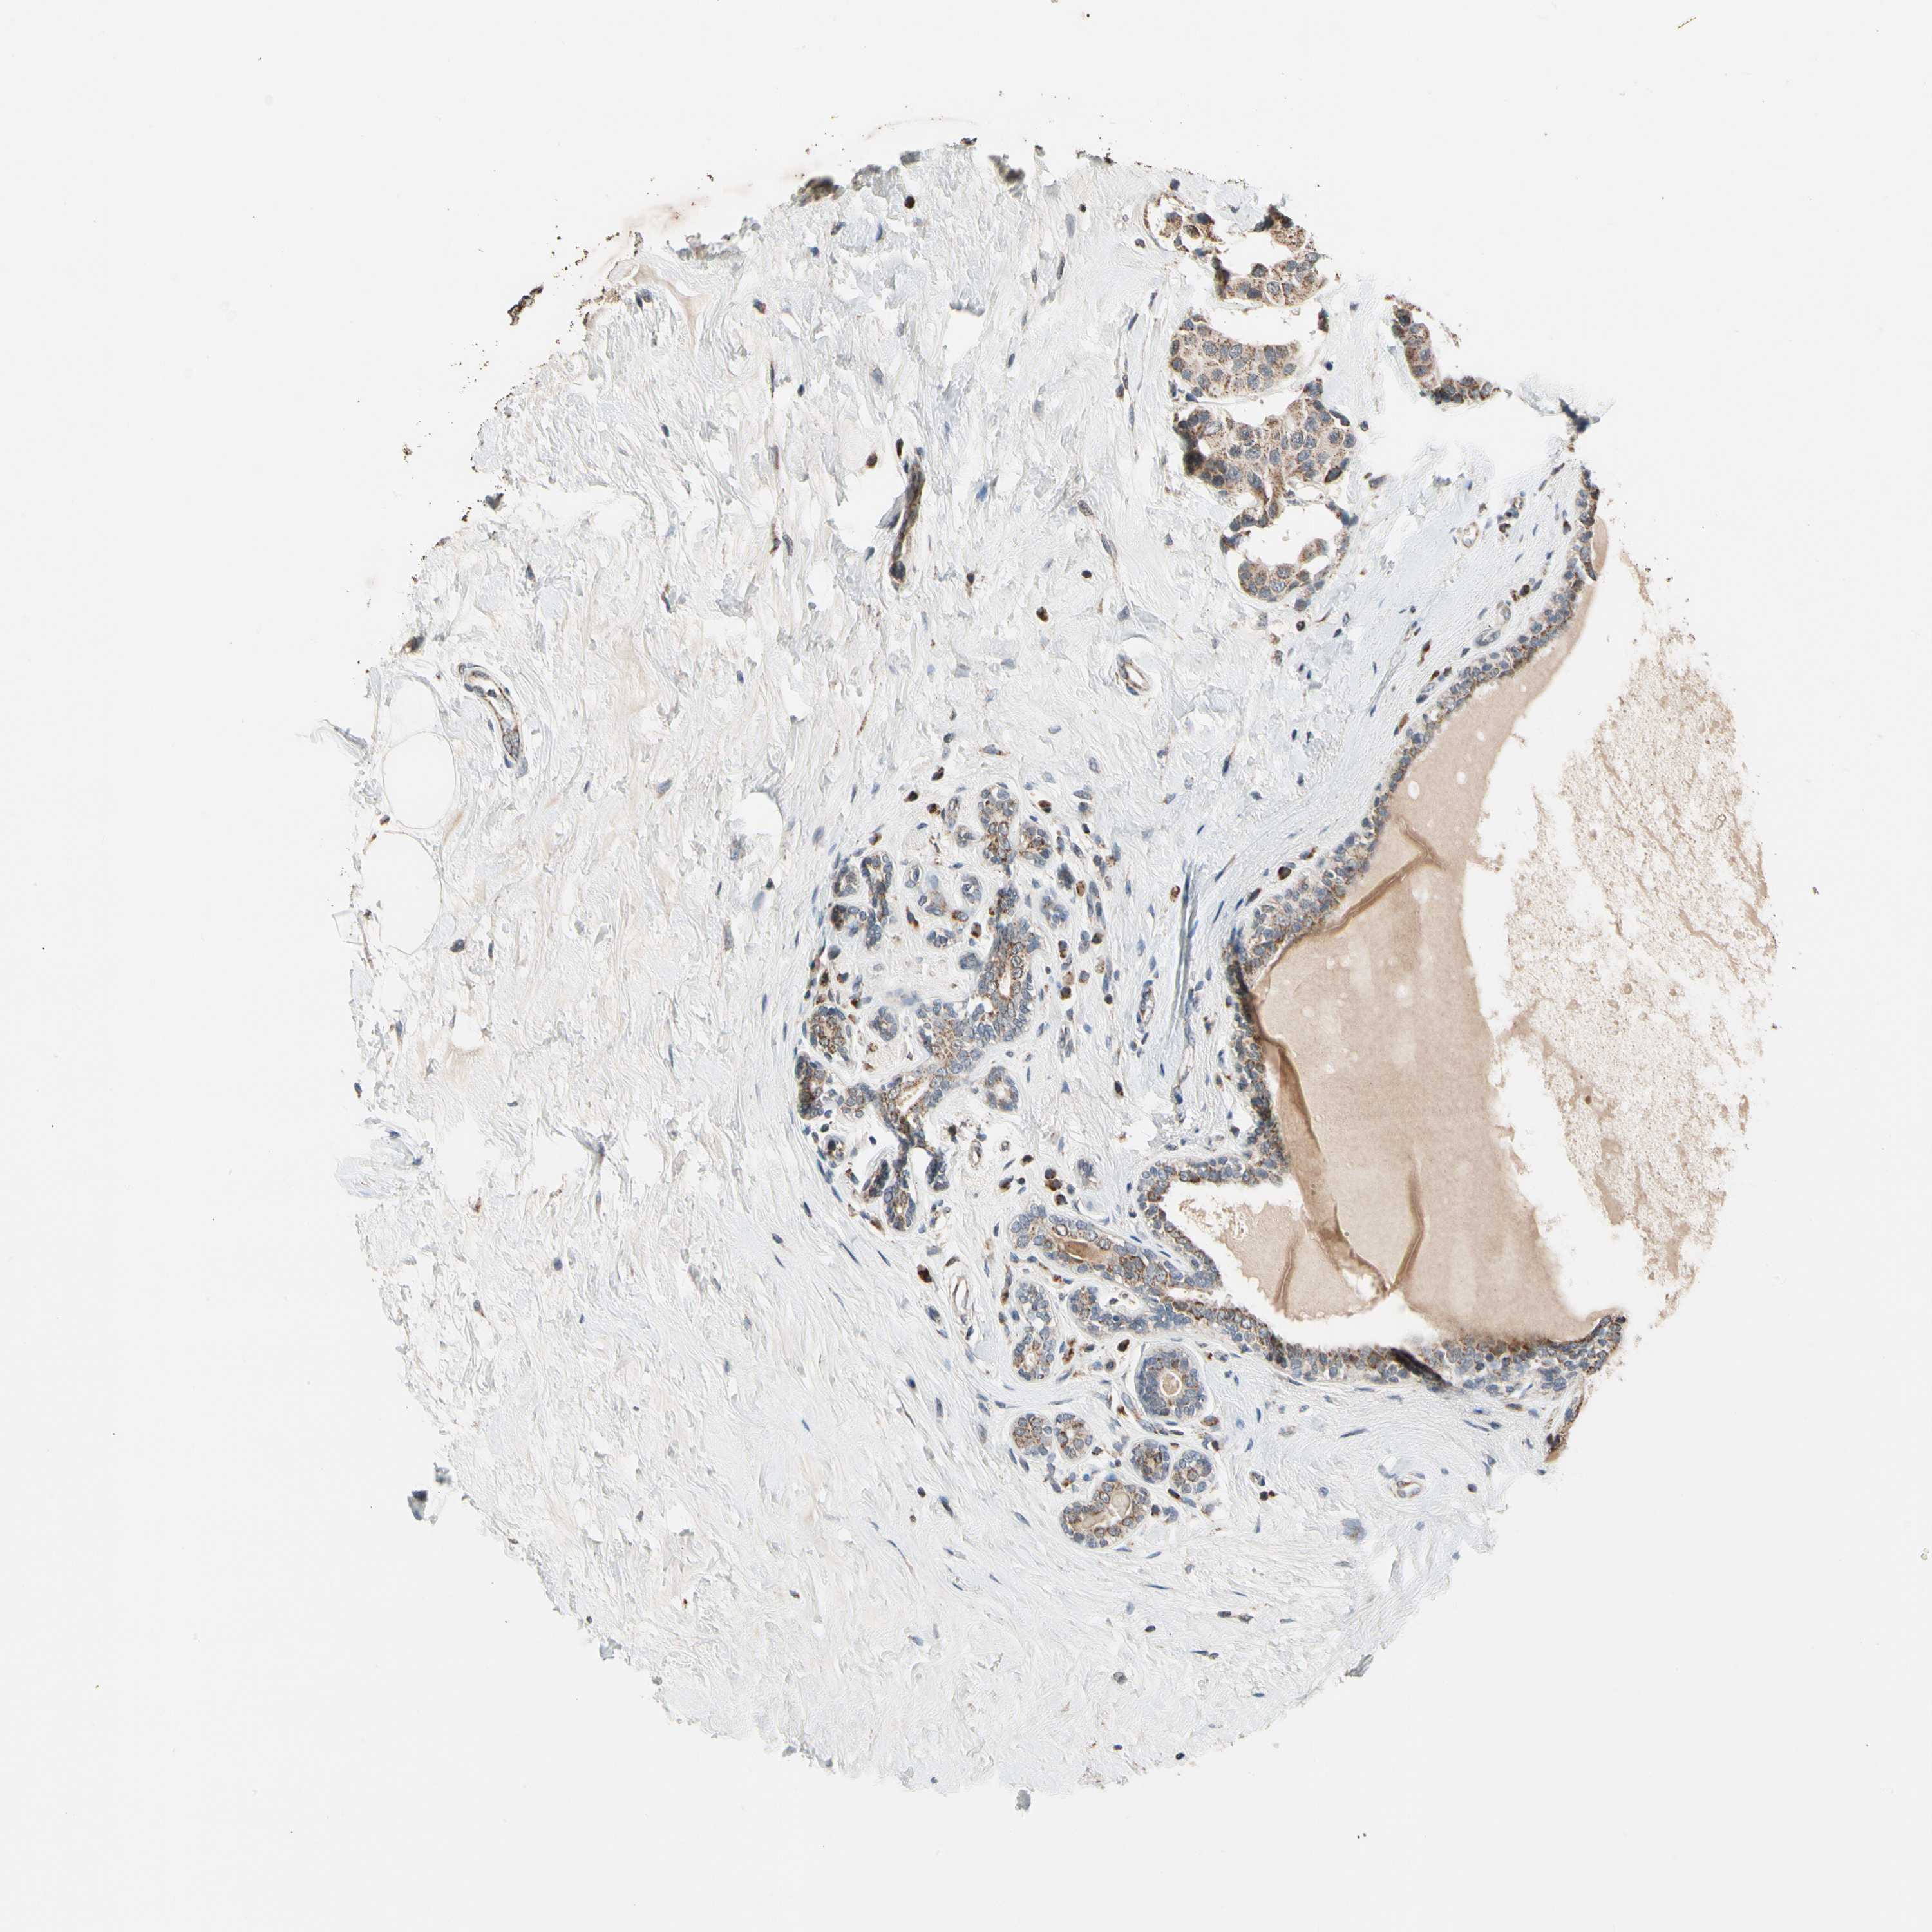

BRCA TCGA BRCA VALIDATION PROTEIN EXPRESSION

Breast cancer

Human cancer